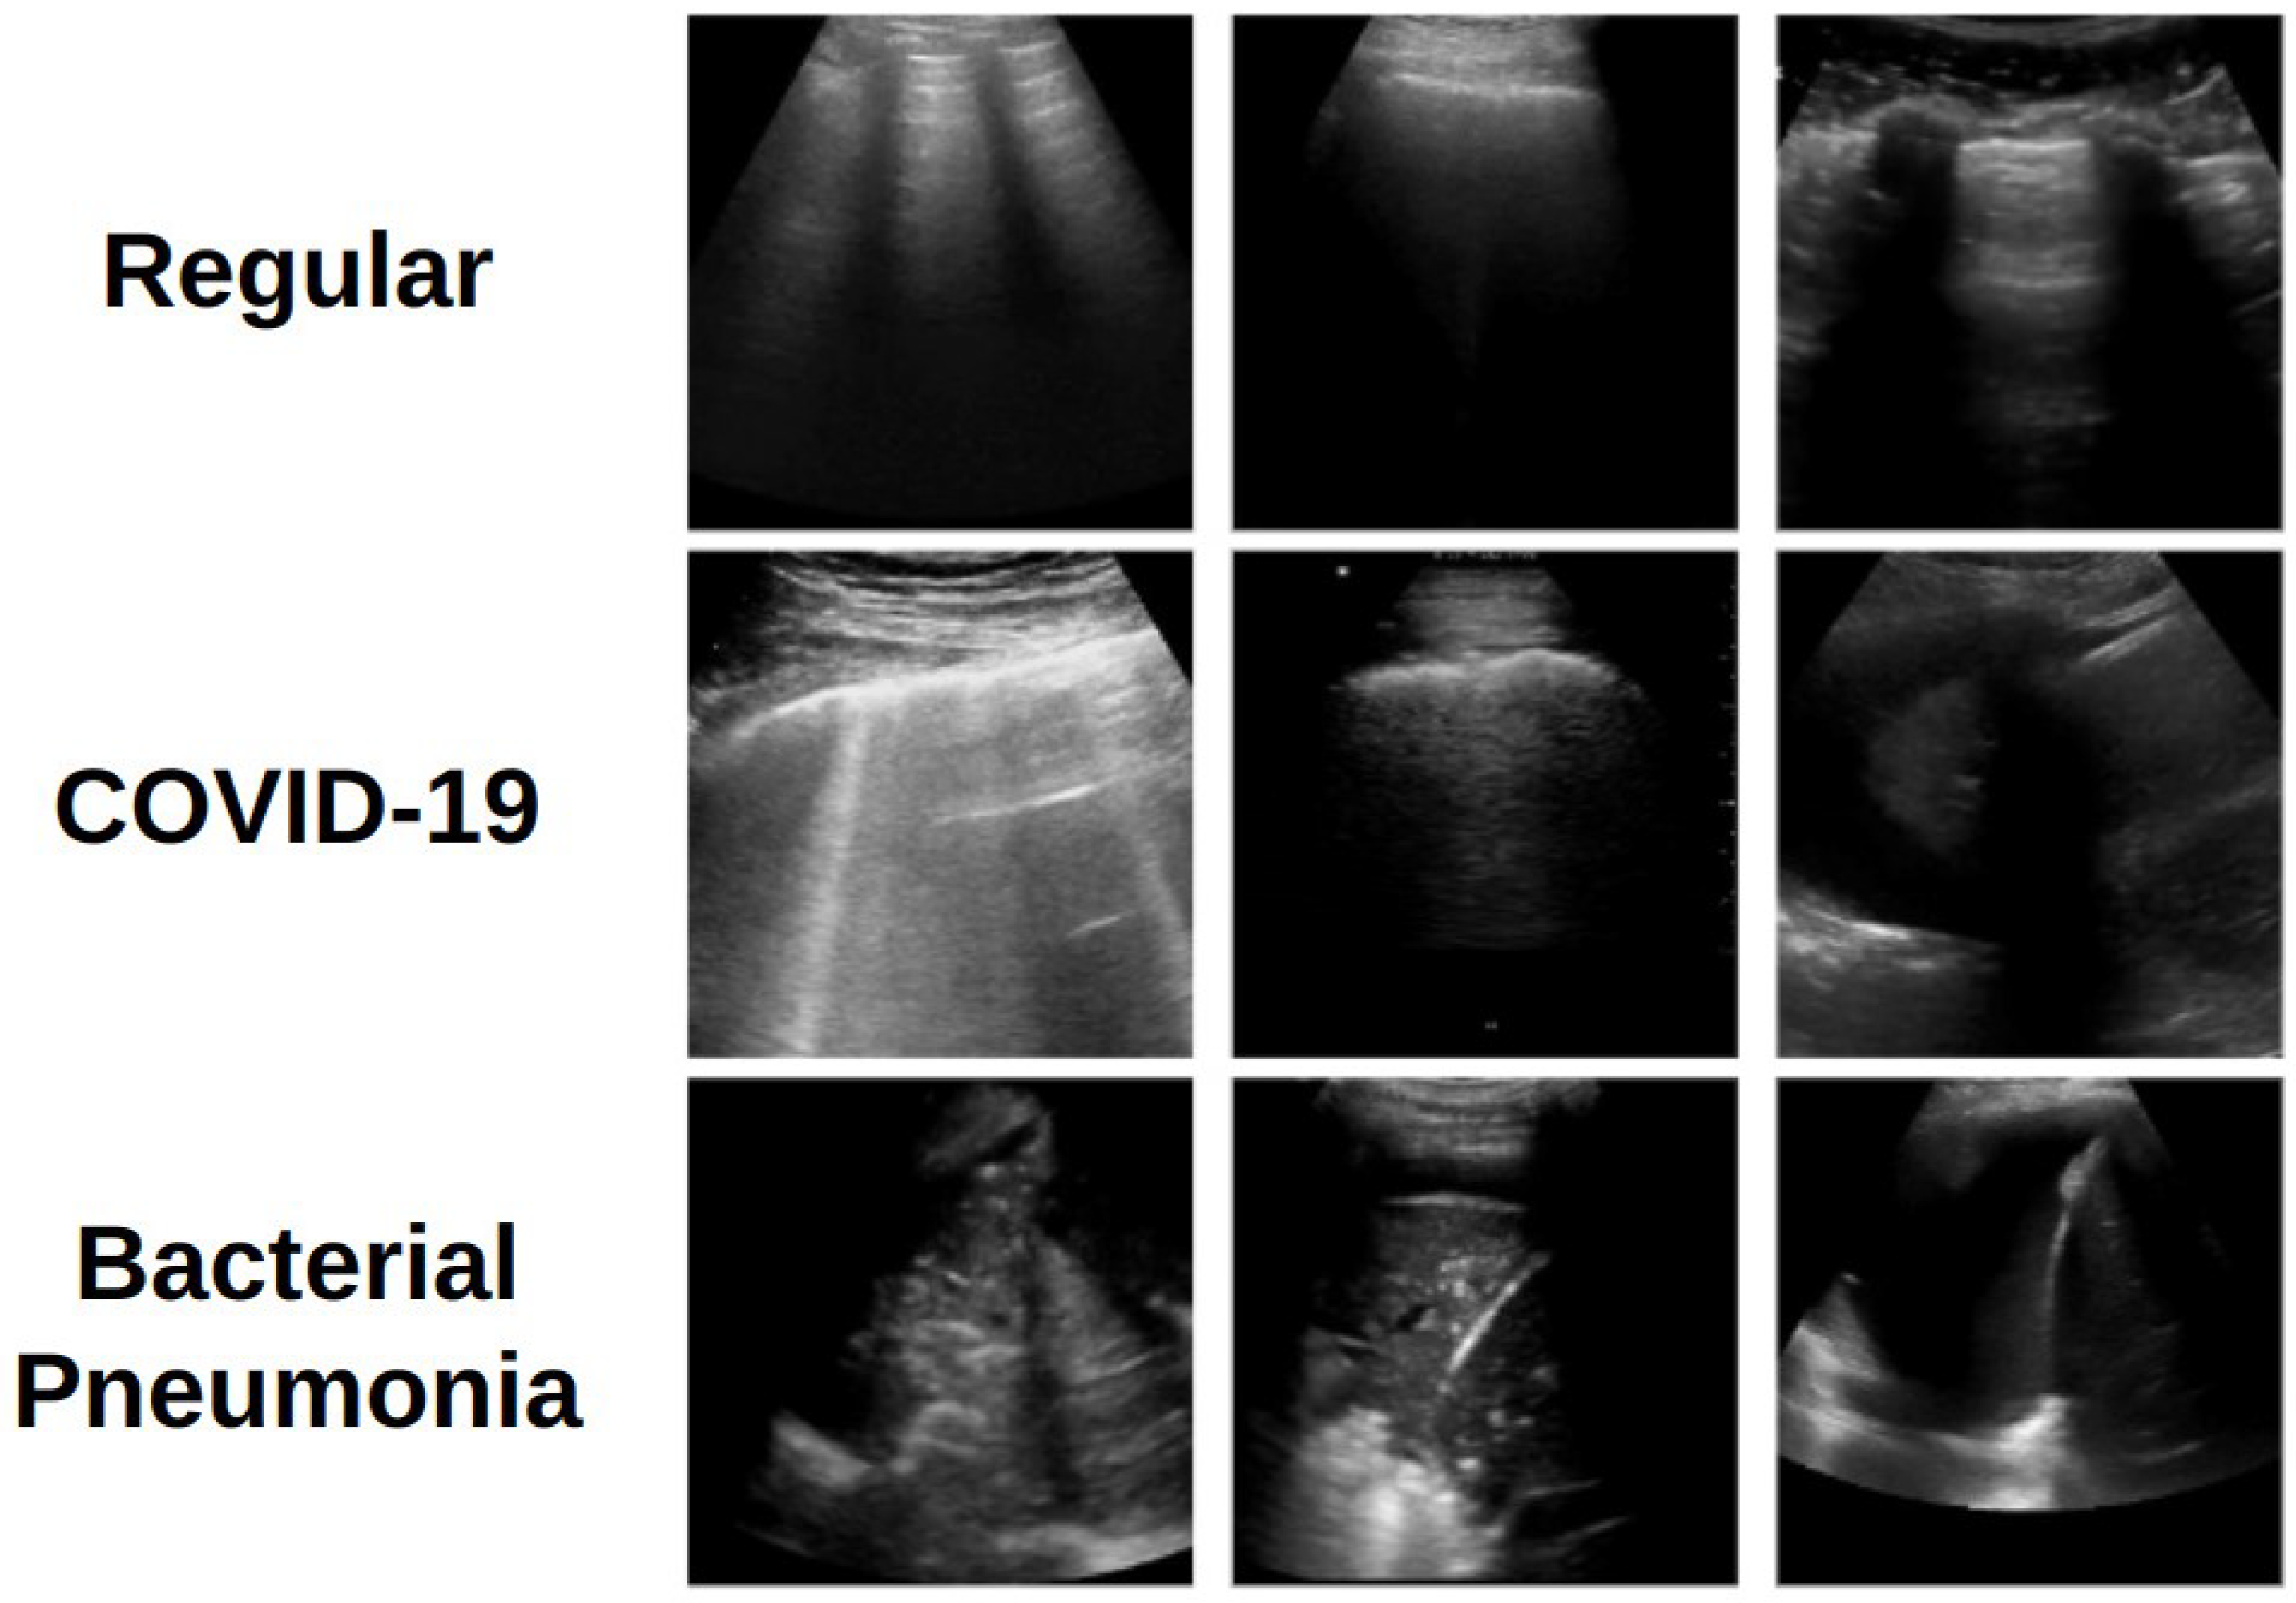

The same preprocessing steps described in [19] have been adopted, with a maximum of 30 frames per video extracted. Each frame was cropped to remove textual annotations and border artifacts and then resized to 128 × 128 pixels to meet computational constraints. Pixel intensities for each image were normalized to the range −1 to +1. A total of 3191 images were extracted (1191 for COVID-19, 708 for bacterial pneumonia, and 1292 for regular/healthy). For training and evaluation, the data were partitioned using stratified 10-fold cross-validation at the patient level, ensuring that no patient appeared in more than one fold. Examples of the preprocessed images are provided in Figure 1.

Figure 1. Examples of LUS images representing each of the three classes.